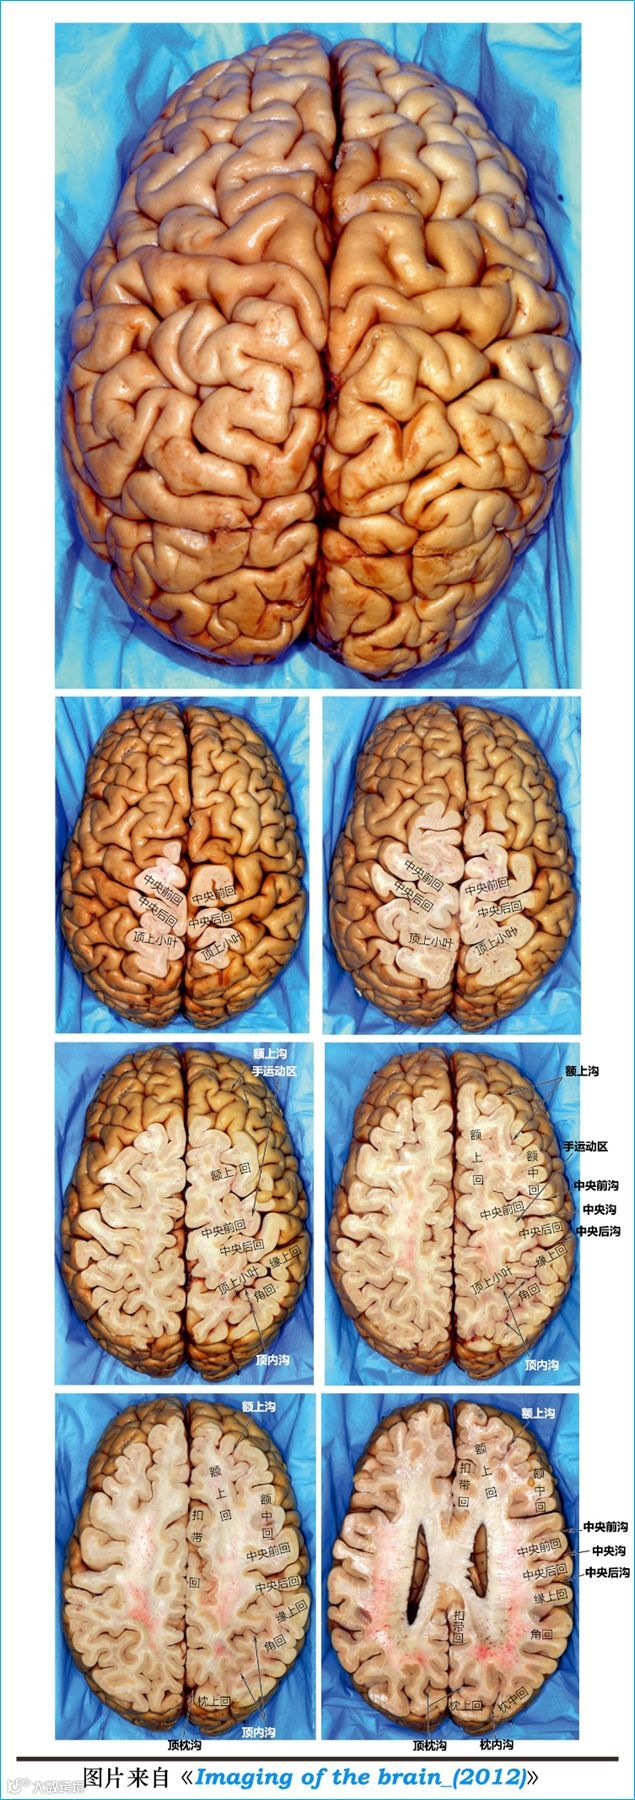

在T2WI反相图学下的颅脑断层解剖(吴晓安老师亲自手动标准)以及标本断层解剖,满满干货,坐在小板凳上,一起学习吧……